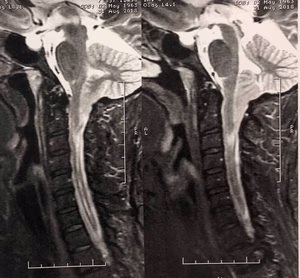

Saiba mais sobre bicos de papagaio, cervicalgia e mielopatia cervical.